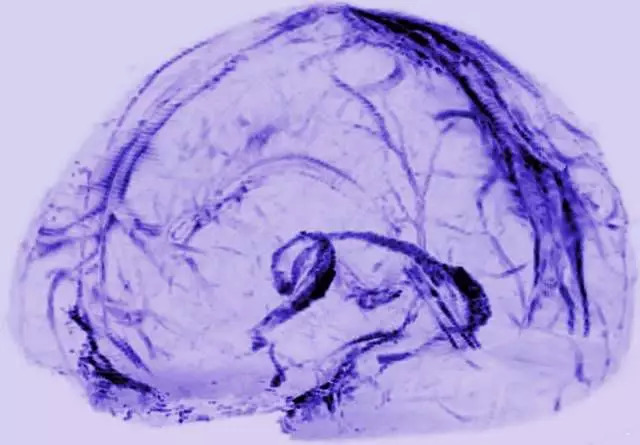

2015年,这一认知被新的实验发现所颠覆,原来大脑和免疫系统之间有着直接的联系。弗吉尼亚大学的研究人员通过实验观察证实,小鼠脑膜上隐藏着淋巴管,可以直接连接到外围的免疫组织。此后2年,研究人员在人体上自然也发现了这一套淋巴组织。

(人脑淋巴管成像图)

这一发现,相当于推翻了此前几十年的医学教科书的结论,同时补全了人体淋巴系统的最后一块,也是最重要的一块领地——大脑。